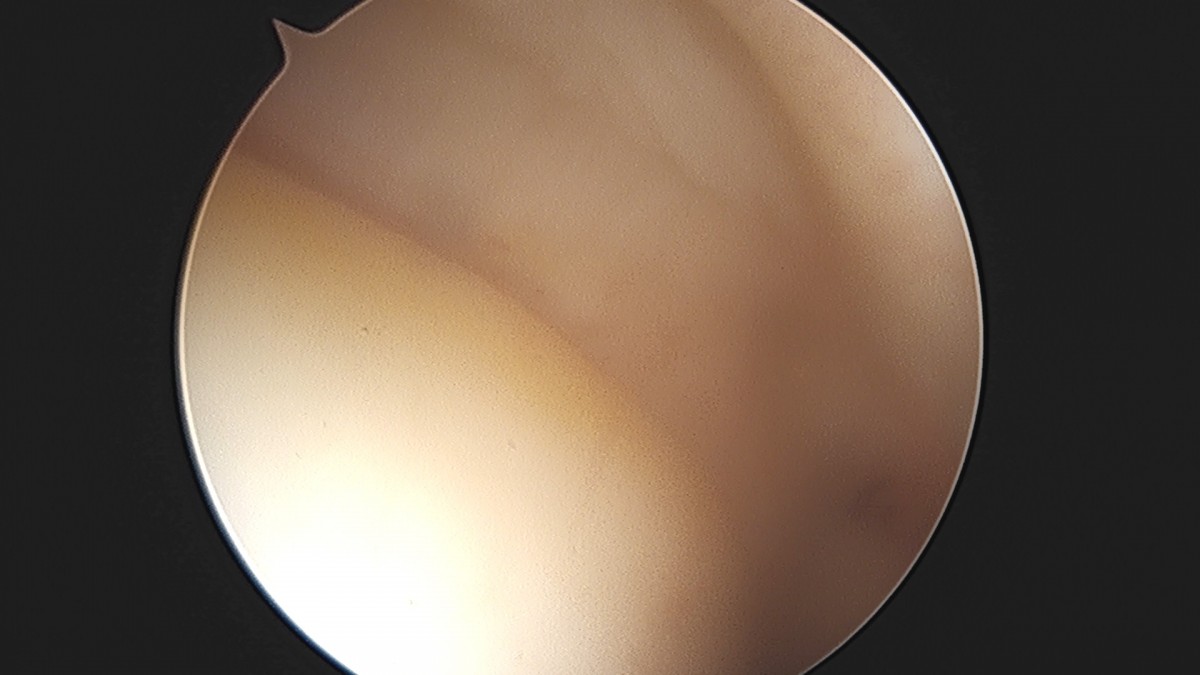

이재상원장님 어깨 견봉하 감압술 및 석회 제거술 이형O 환자

dae765e4d9ac96aee867c9d6292d8784_1758004811_5774.jpg

dae765e4d9ac96aee867c9d6292d8784_1758004812_1603.jpg

dae765e4d9ac96aee867c9d6292d8784_1758004812_7437.jpg

dae765e4d9ac96aee867c9d6292d8784_1758004813_474.jpg

dae765e4d9ac96aee867c9d6292d8784_1758004814_0674.jpg

dae765e4d9ac96aee867c9d6292d8784_1758004814_6645.jpg

dae765e4d9ac96aee867c9d6292d8784_1758004815_2588.jpg

dae765e4d9ac96aee867c9d6292d8784_1758004815_8533.jpg

dae765e4d9ac96aee867c9d6292d8784_1758004816_4696.jpg

dae765e4d9ac96aee867c9d6292d8784_1758004817_0509.jpg